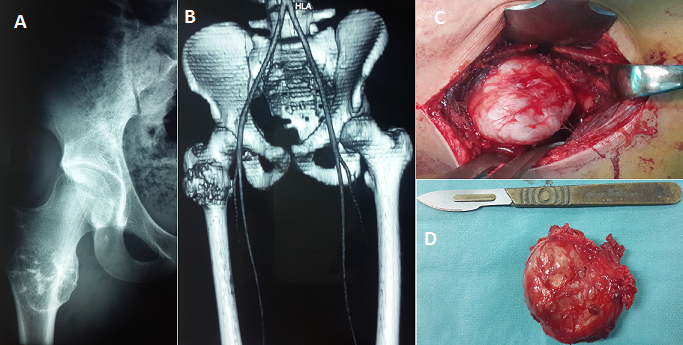

L'ostéochondrome ou exostose est la tumeur osseuse primaire bénigne la plus fréquente, elle contient à la fois de l'os et du cartilage et siège le plus souvent au niveau des métaphyses des os long. Ces tumeurs sont le plus souvent asymptomatiques, en fonction de leur taille, leur emplacement et de leur localisation; leur siège au niveau du fémur proximal est rarement rencontré car la plupart sont généralement asymptomatique. Nous rapportons un cas rare d'ostéochondrome de la région inter-trochantérienne du fémur chez un patient âgé de 35 ans, présentant depuis 1 année une tuméfaction de la face externe du tiers supérieur de la cuisse droite, indolore, sans notion de traumatisme ni d'antécédents médicaux ou chirurgicaux. L'examen physique a mis en évidence une masse ferme, indolore, immobile, sans signes cutanées associées; la mobilité de la hanche est normale et le reste de l'examen physique, notamment l'examen vasculo-nerveux du membre inférieur droit, est sans particularité. Les radiographies standards (A) et la TDM (B) ont été réalisés pour évaluer le siège, l'étendue et la nature de la tumeur. Le patient a bénéficiée d'une exérèse chirurgicale de la masse (C,D) et l'examen anatomopathologique a confirmé la nature histologique de la tumeur. Le patient a été maintenu en décharge pendant 2 semaines avec reprise de la marche à la 4ème semaine postopératoire. A 12 mois de recul, l'examen clinique et radiographique n'a pas objectivé de signes de récidive.